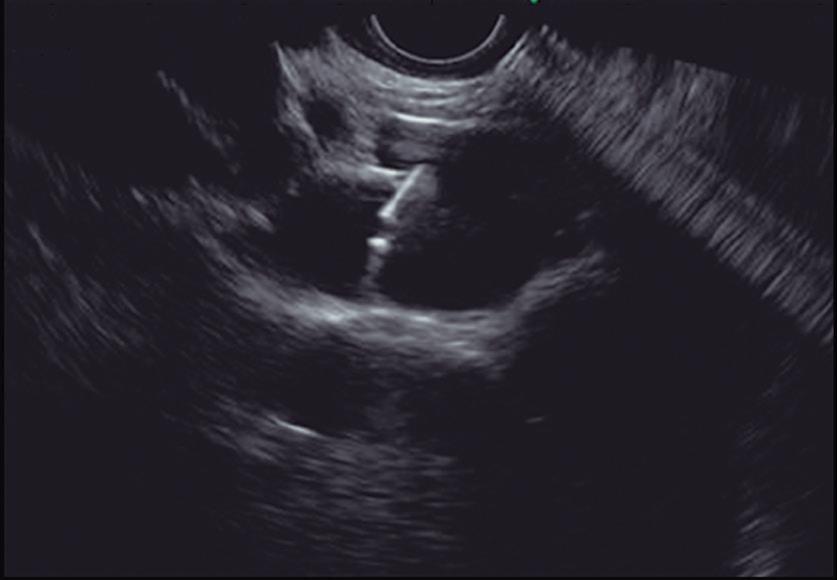

Evaluación endoscópica e histológica

La endoscopía superior es un procedimiento fundamental para el diagnóstico, la evaluación de la respuesta al tratamiento y el monitoreo a largo plazo de la actividad de la EEo. Los hallazgos endoscópicos típicos incluyen edema (reducción de vascularidad), anillos esofágicos fijos, exudados blancos, surcos longitudinales, estenosis, estrechamiento de la luz esofágica, friabilidad de la mucosa (mucosa en papel crepé) y una consistencia firme de la mucosa al realizar biopsias (signo de “tracción" o "resistencia”) en pacientes con fibrosis (Figura 1). Estos hallazgos no son patognomónicos y no constituyen un criterio diagnóstico; sin embargo, cuando se evalúa de forma cuidadosa, en la gran mayoría de los casos se pueden observar.19-21

Es imperativo llevar a cabo una exploración endoscópica minuciosa en todos los casos de sospecha de patología esofágica. En el contexto de la EEo, esto requiere dedicar un tiempo adecuado a la visualización completa del esófago tras la intubación, evitando desplazar o raspar los exudados, insuflando adecuadamente el esófago, eliminando cuidadosamente mucosidad, saliva o detritus, y evaluando el calibre esofágico. Esta evaluación puede incluir la retroflexión en la unión gastroesofágica para estimar el diámetro de las estenosis en dicha región.22

Un elemento fundamental en la evaluación de la EEo es la aplicación del puntaje de referencia endoscópica para la esofagitis eosinofiílica (EREFS por sus siglas en inglés: Eosinophilic Esophagitis Endoscopic Reference Score).20 El acrónimo EREFS también refleja las cinco características endoscópicas principales de la EEo: Edema, anillos esofágicos (Rings), Exudados, surcos longitudinales (Furrows) y estenosis (Stricture). Estas características se clasifican según su severidad mediante un sistema de puntuación que oscila entre 0 y 9, considerándose la región esofágica con la alteración más marcada. El EREFS cuenta con validación interna y externa, y ha demostrado una elevada capacidad para diferenciar la EEo de otras patologías no relacionadas en poblaciones pediátricas y adultas, además de correlacionarse con la respuesta terapéutica.23-25 Por estos motivos, el EREFS constituye un sistema estandarizado para la evaluación

En el panel A se observa un esófago con edema difuso y pliegues longitudinales; en el panel B se aprecia edema con pliegues y exudados blanquecinos; en el panel C se evidencia un estrechamiento luminal acompañado de anillos esofágicos y exudados; y en el panel D se muestra un desgarro mucoso posterior a la dilatación con bujía de Savary, hallazgo esperado tras este procedimiento terapéutico.

Figura 1. Características endoscópicas de la esofagitis eosinofílica